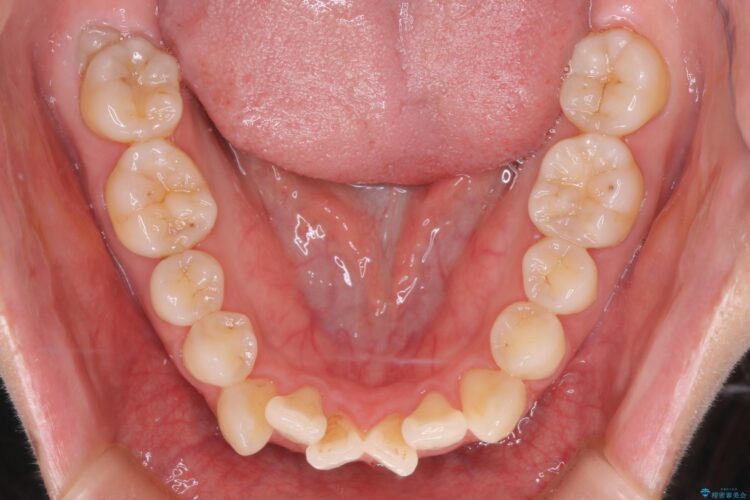

上の前歯のデコボコを主訴にご来院された患者様です。

重度の叢生が認められたため、上下左右4番目の歯を抜歯しワイヤー矯正治療を行いました。